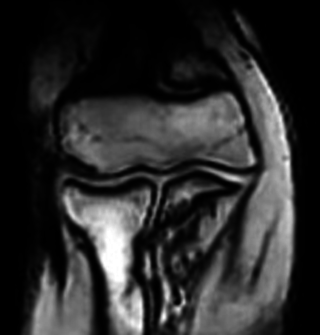

次に我々が大学で実際に検診に使用している0.2テスラの四肢専用(手足専用)MRI の肘の画像です。もちろんしかるべき承認をうけて発売されている機械です。

写真2 0.2T 四肢専用MRI (販売品)の画像

これは13歳の少年で、骨端線がとじておらず、まだ子供の骨格です。

さきほどと同じ場所を撮影しています。全体に少しさきほどより黒っぽくは見えますが、ほとんど撮影シーケンスという条件の違いによるものです。

こちらも骨の形、軟骨、骨髄の様子が大変よくわかります。

現在の検診はこの機械を使ってこの画質で診断をしています。